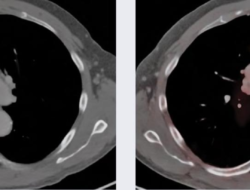

Discover the transformative power of psma pet scans near me, where cutting-edge technology meets expert…

psma pet scan near me Discover Local Solutions

With psma pet scan near me at the forefront, uncover the paramount advancements in cancer…